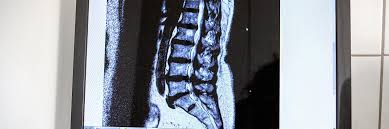

Die wichtigsten Tipps im Umgang mit Spinalkanalstenose. Durch Abnutzungserscheinungen der kleinen Wirbelgelenke der Bandscheiben im Alter durch Bewegungsmangel oder Veranlagung daraus folgt kein langer Spaziergang das Kreuz tut weh Schmerzen ziehen bis in die Beine. Viele Patienten mit einer Spinalkanalstenose klagen neben Schmerzen in den Beinen beim Gehen über eine Schwäche und ein Schweregefühl der Beine.

Die wichtigsten Symptome einer Spinalkanalstenose sind belastungsabhängige Rückenschmerzen und Beinschmerzen hauptsächlich beim Gehen Stehen und. Bei einer Spinalkanalstenose kommt es zu Schmerzen im Bein beim Gehen Tipps zur Vorbeugung und Selbsthilfe alles zu Symptomen. Meine Schmerzen die in die Beine ausstrahlten waren sofort nach der OP weg.

Wenn Schmerzen im Bein sehr gefährlich sind. Die Belastungsfähigkeit ist herabgesetzt. Kreuzschmerzen und ein Ausstrahlen dieser Schmerzen in die Beine sind Symptome einer Spinalkanalstenose.